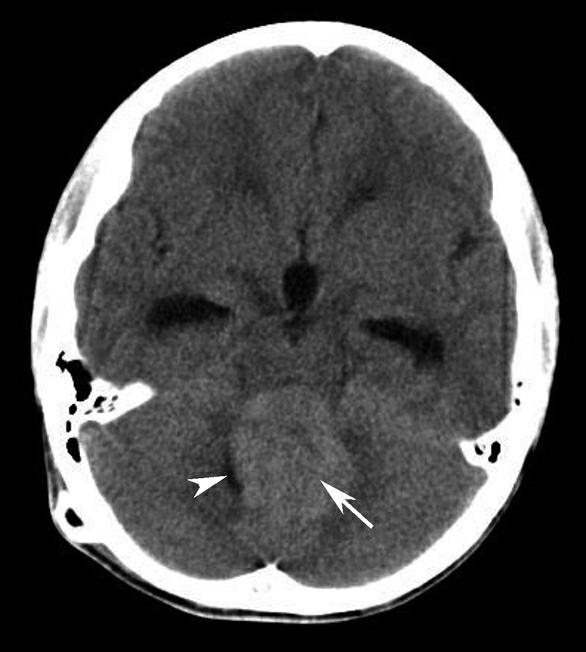

破裂孔、卵圆孔、棘孔及斜坡等均为重要的解剖结构,临床常见疾病如鼻咽癌常侵犯上述结构(图1-2-3)。颈静脉孔区较常见的肿瘤为颈静脉球瘤,常伴有颈静脉孔及其邻近骨质的破坏(图1-2-4)。

图1-2-3 鼻咽癌颅底骨质破坏

A.横断面;B.横断面(骨窗)

骨窗示左侧岩尖、斜坡、左侧蝶骨大翼骨质破坏、受侵(白箭),肿瘤经破裂孔侵入颅内(黑箭头)